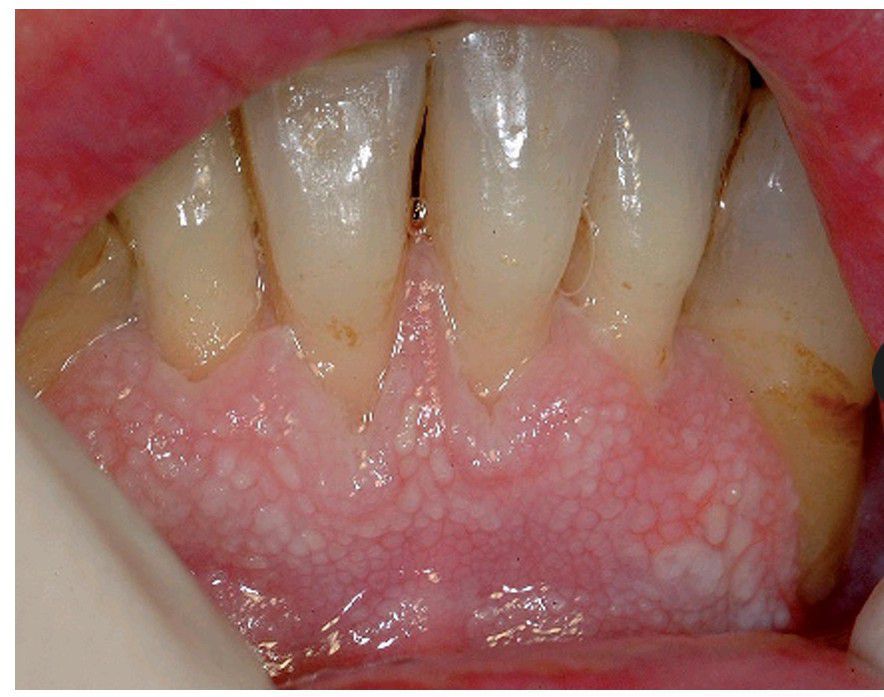

Speckled leukoplakia

Speckled leukoplakia: often a potentially malignant lesion